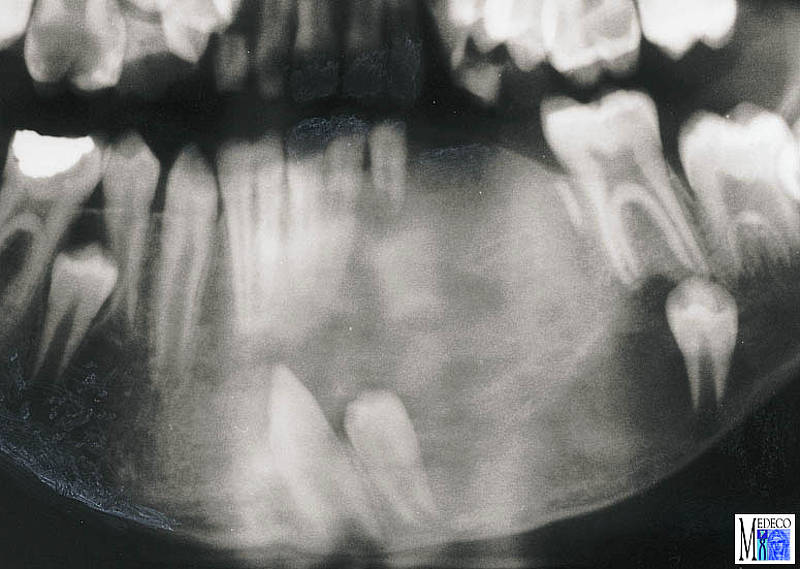

2013Vets Ossifying fibroma inside an old dog's mouth

Epulis, ossifying epulis, fibromatous epulis, and fibroosseous epulis are all terms that. Den uppkommer snabbt och kan bli någon. Se mai numeste si nodul fibromatos intramural.

Odontogene Tumoren